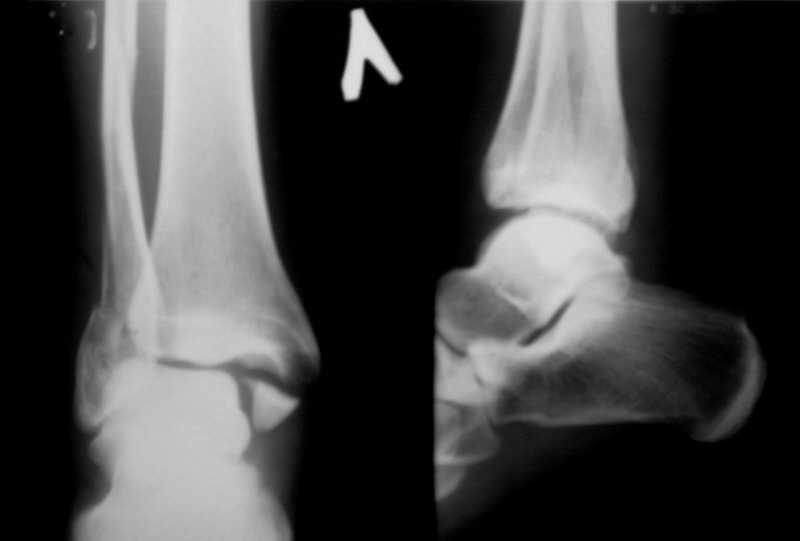

Перелом лодыжекКонтрольные рентгенограмы сделаны с нарушением укладок для стандартных проекций. Переделайте рентгенснимки и догда можно будет о чем-то иметь дискуcсию.

Рентгенограммы не сделаны в строго боковой и передне-задней проекциях.

Но и здесь видно, что внутренняя лодыжка "висит" - это говорит об интерпозиции. Выполняйте открытую репозицию и металлостеосинтез.

Можно сделать прямую с внутренней ротацией в 20 гр - еще лучше будет видно. Внутренняя лодыжка на боковом снимке не так уж плохо стоит. В любом случае - надо сделать нормальные снимки.

Вопрос к автору сообщения - эти лодыжки в задней гипсовой лонгете, судя по снимкам, или показалось?

Вот рентгенконтроль на 7-е сутки после репозиции.

Стандартными снимками считается прямая, боковая и мортиз!!!, а так трудно гадать, насколько потеря длины малоберцовой. На боковом снимке не сопоставленный перелом медиальной лодыжки и перелом заднего края без смещения.